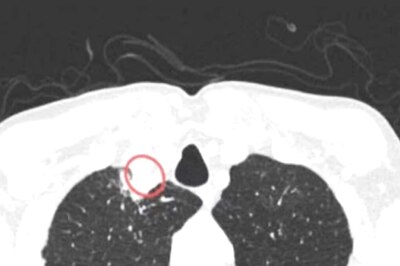

A report by the Medical Mycology Case journal said that the patient went to see a doctor after symptoms like hoarse voice, cough, fatigue and difficulties swallowing persisted for three months.